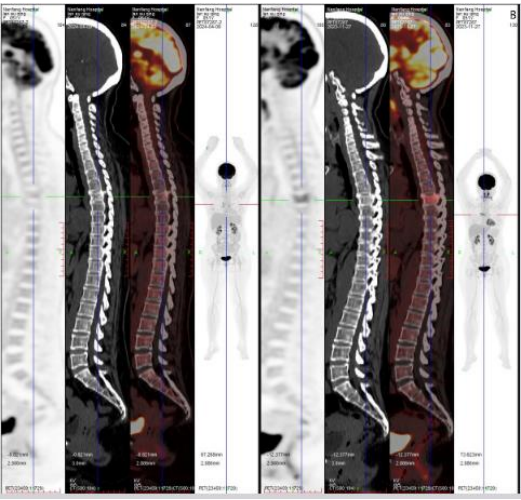

A 52-year-old woman presented with progressive low back pain and bilateral lower limb weakness. Physical examination was notable only for lumbosacral tenderness. Laboratory testing showed an elevated EBV DNA load (6.84 × 10³ copies/mL) and mildly increased LDH. PET-CT identified hypermetabolic lesions in the T5 vertebra and multiple lymph nodes (Figure 1A).

Figure 1: PET/CT findings of the patient with plasmablastic lymphoma

(A) Baseline showing hypermetabolic lesions in T5 and paravertebral regions

After four cycles, PET-CT demonstrated complete metabolic remission (Figure 1B).

(B) After four cycles of daratumumab plus CHOP, complete metabolic remission

Two additional cycles were administered, followed by autologous stem cell transplantation on July 12, 2024. Three months later, PET-CT confirmed sustained complete remission (Figure 1C).

(C) Three months after ASCT, sustained complete remission observed.